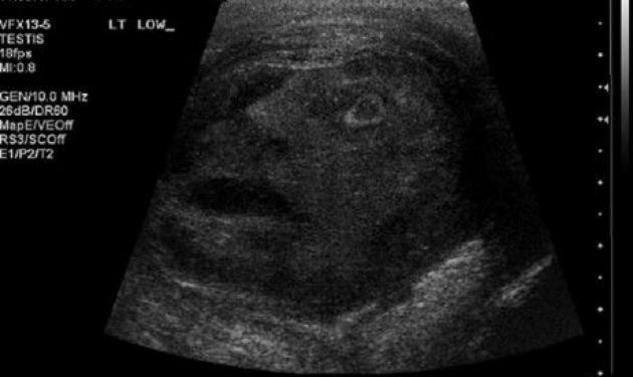

Καναδοί ερευνητές εξετάζουν τις παράξενες εικόνες που παρουσίασε υπέρηχος σε όγκο στους όρχεις ασθενή. Ο λόγος που τον εξετάζουν με τόση προσοχή δεν είναι μόνο για να καταφέρουν να θεραπεύσουν τον ασθενή αλλά κυρίως γιατί ο όγκος μοιάζει με κεφάλι που τους κοιτάει...

''Ήταν σαν η τέχνη να πηγάζει μέσα από τους όρχεις του ασθενούς'', δήλωσε γιατρός στο ''National Post''. Και συνέχισε: ''Πρόκειται για ένα καταπληκτικό και διασκεδαστικό εύρημα'' - που μάλιστα δημοσιεύτηκε στο περιοδικό ''Urology'' με τίτλο ''The Face of Testicular Pain''. (σ.σ. Το πρόσωπο του πόνου των όρχεων.)

Το προσωπικό του νοσοκομείου όπου πραγματοποιήθηκε ο συγκεκριμένος υπέρηχος, που αποκάλυψε ένα πρόσωπο στο ιδιαίτερο αυτό σημείο του ασθενούς, σοκαρίστηκε και εξεπλάγειν.

Δεν είναι και το πιο συνηθισμένο να παρακολουθείς μέσα από έναν υπέρηχο ένα κεφάλι με το στόμα ανοιχτό και τα μάτια γουρλωμένα, να σε κοιτάζει μέσα από έναν όγκο!

Όπως ανέφεραν όμως, οι γιατροί πρόκειται απλά για κάποιον καλοήθη όγκο... στο επίμαχο σημείο!